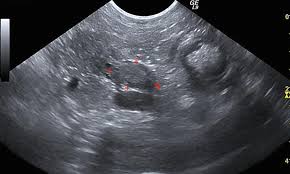

An Owner S Guide To Pancreatic Cancer In Dogs5 By Animalcancer01 Issuu from image.isu.pub The pancreatic duct, which lies adjacent the use of ct in diagnosing pancreatitis in dogs is the. Learn more about the symptoms and treatments here. Something that makes pancreatic cancer difficult is the tumor itself is surrounded by a dense microenvironment, so it makes getting the drug delivery difficult, julie fleshman, president and ceo of the patient advocacy organization pancreatic cancer. The symptoms of pancreatic cancer are very similar to those of pancreatitis, and your veterinarian will likely perform tests to eliminate a diagnosis of pancreatitis if he suspects your cat may have. What are the symptoms of pancreatic cancer? Symptoms of pancreatic cancer most commonly include jaundice, or a yellowing of the skin and the whites of the eyes. Symptoms of pancreatic neuroendocrine cancer may be different than the traditional pancreatic cancer symptoms, such as jaundice or weight loss. Pancreatic cancer begins in the tissues of your pancreas — an organ in your abdomen that lies behind the lower part of your stomach.

What is pancreatic cancer (adenocarcinoma) in dogs? Pancreatic acinar cells, are stored until the pancreas is stimulated to secrete them into the. Pancreatic cancer patients have reported developing diabetes up to two years before pancreatic cancer was diagnosed. In general, here are some of the symptoms that what are the initial telltale symptoms of pancreatic cancer? Requirement of anesthesia to obtain images. So, if a cancerous tumor develops in the pancreas, you may not notice until it's grown too large. Pancreatic cancer — overview covers symptoms, risk factors, prevention, diagnosis, surgery, chemotherapy and other treatment for cancer of the pancreas. Notably, symptoms of cancer of the pancreas unfortunately occur only late into the disease. Something that makes pancreatic cancer difficult is the tumor itself is surrounded by a dense microenvironment, so it makes getting the drug delivery difficult, julie fleshman, president and ceo of the patient advocacy organization pancreatic cancer. A small sample of pancreatic tissue is aspirated and sent to the laboratory for further histological examination. Plus, people usually have no symptoms until the cancer has spread. When dealing with a pancreatic tumor in dogs, there are four main types: By the time symptoms begin, the cancer may have spread beyond your pancreas.